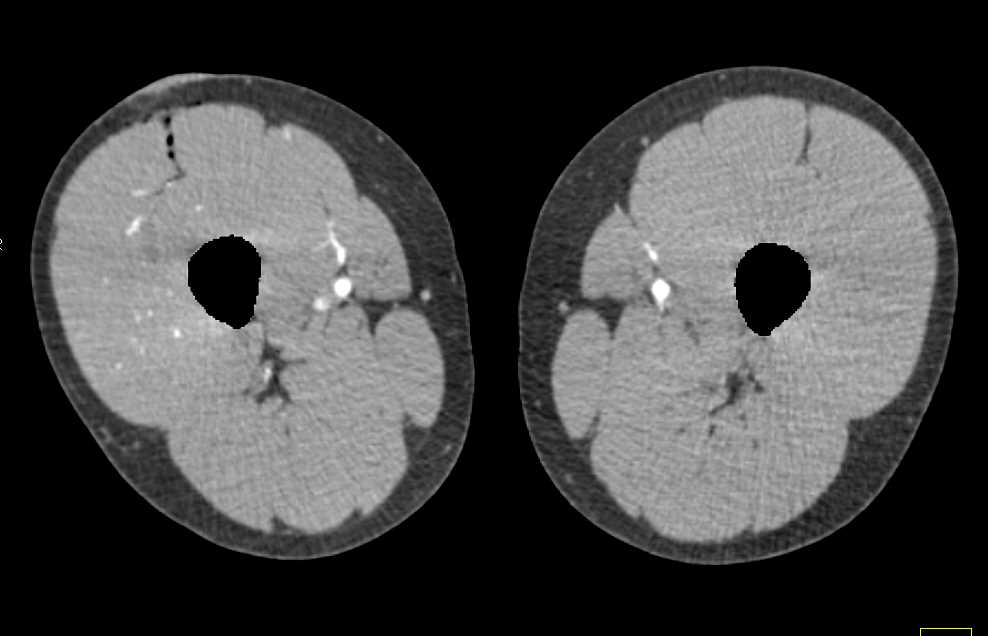

Occluded Left Common Iliac Artery by Clot